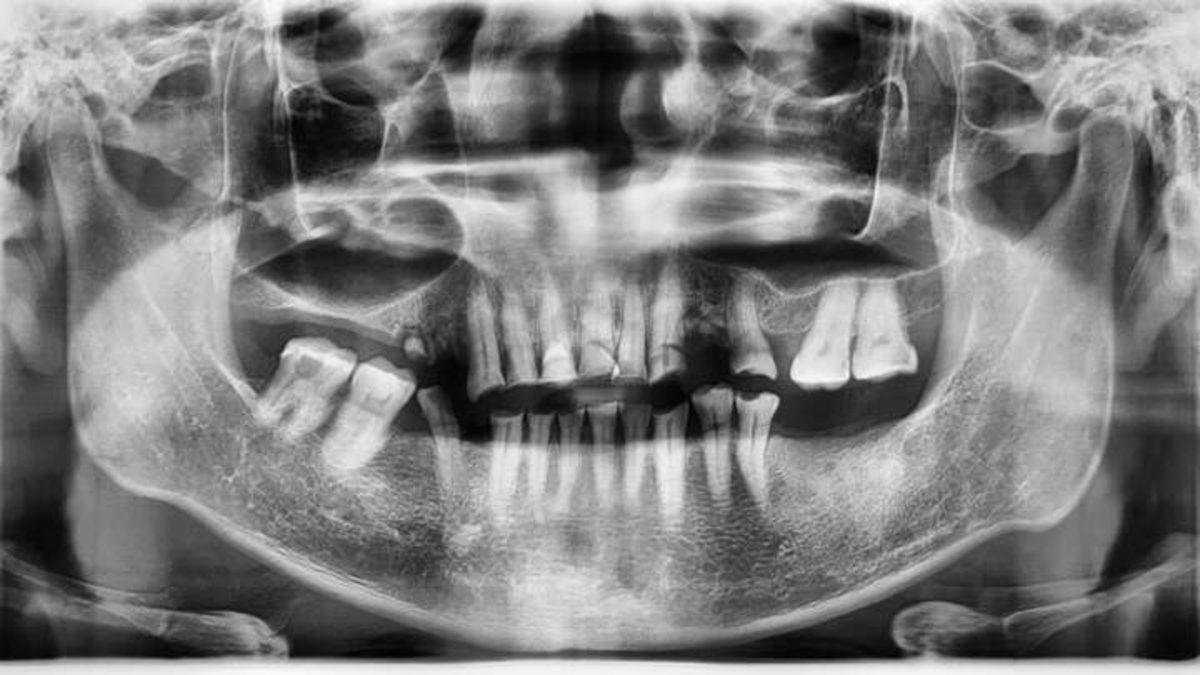

Byers'ın avukatı, ünlü ismin üst çenesinde sadece iki dişinin kaldığını, alt çenesinin büyük kısmının alındığını, kafatasında delikler oluşmaya başladığını ve kemiklerinin de parçalanmakta olduğunu söyledi.